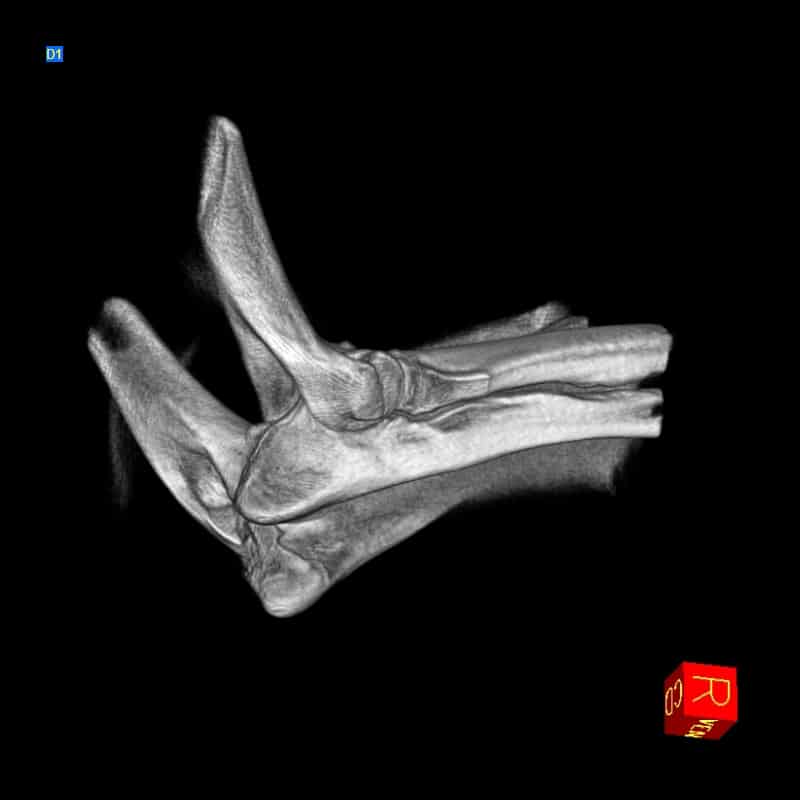

Arthroscopy

We have advanced diagnostic and arthroscopic skills to help fix elbow dysplasia, medial coronoid disease, ununited anconeal process, and OCDs.